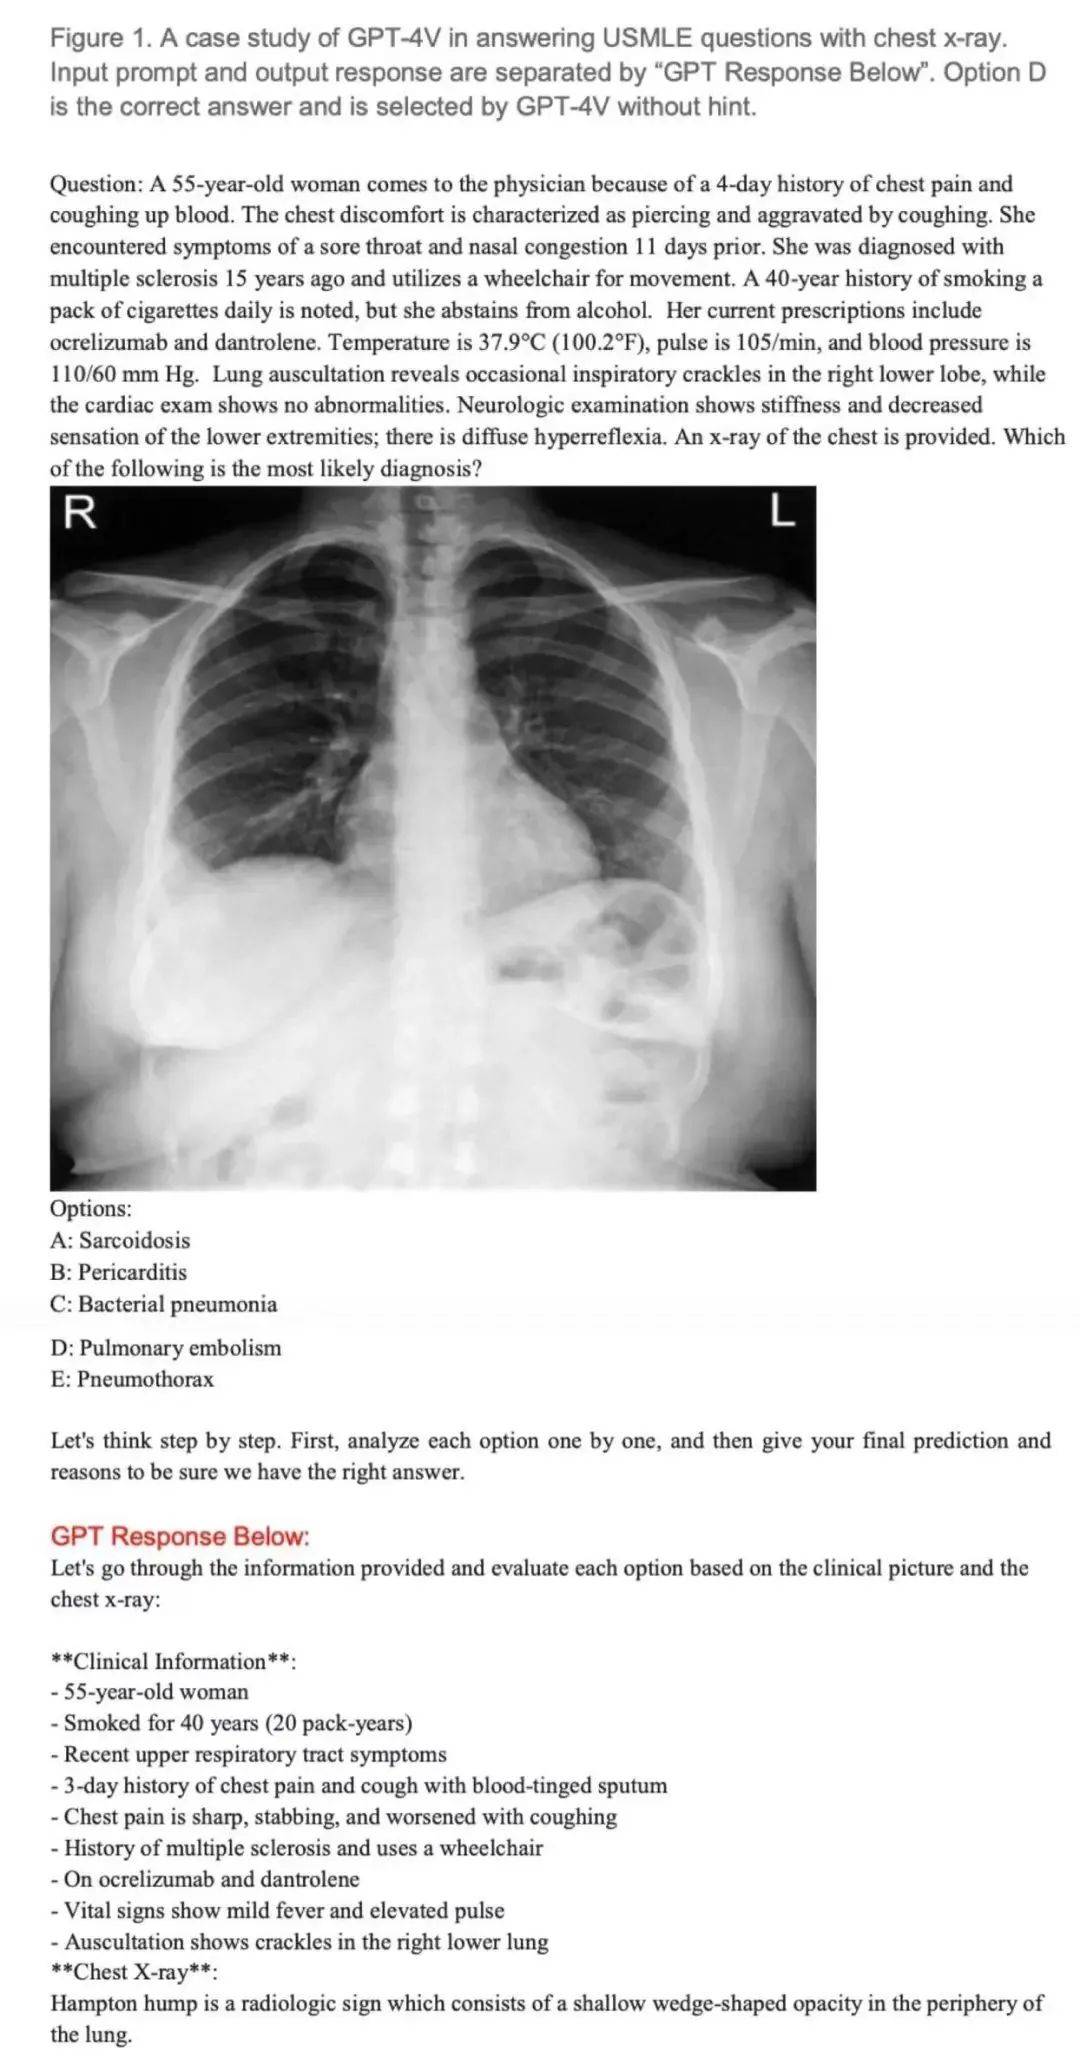

研究测试了GPT-4V回答美国医学执照考试题的能力,特别是题目包含图像的考题 —— 这对医疗人工智能系统来说一直以来都是一项挑战。

用美国医学执照考试(USMLE)中包含图像的考题测试 GPT-4V。